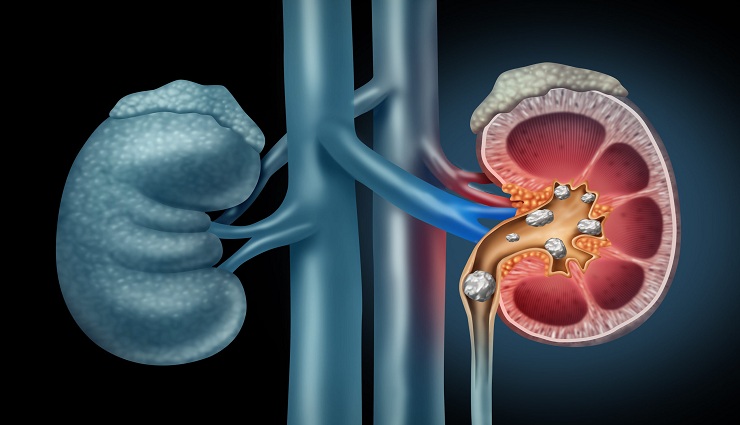

சென்னை: சிறுநீரக கல்லை தடுக்க என்ன செய்வேண்டும் என்றால் நாம் உண்ணும் உணவில் கால்சியம், பாஸ்பேட், யூரியா, ஆக்சலேட் போன்ற தாது உப்புகள் உள்ளன.

உணவு செரிமானம் ஆன பின்னர் இவை சிறுநீரில் வெளியேறிவிடும், சில நேரங்களில் ரத்தத்தில் இவைகளின் அளவு அதிகரிக்கும் போது சிறுநீரில் வெளியேறுவதற்கு சிரமப்படும்.

இவை ஒன்று திரண்டு சிறுநீர்ப் பாதையில் கற்களை உருவாக்குகின்றன. எனவே சிறுநீரக கல் கரைக்க என்ன செய்யலாம் என்பதை பற்றி பார்ப்போம். முதலில், சிறுநீரகத்தில் கல் பிரச்சனை இருப்பது தெரிந்தால் உடனடியாக நீர்ச்சத்து நிறைந்த காய்கறிகள் மற்றும் பழங்களைச் சாப்பிட வேண்டும். அதிலும், குறிப்பாக புடலங்காய் சுரைக்காய் பரங்கி வாழைத்தண்டு வெள்ளரிக்காய் ஆகியவற்றை உணவில் சேர்த்துக் கொள்ள வேண்டும்.